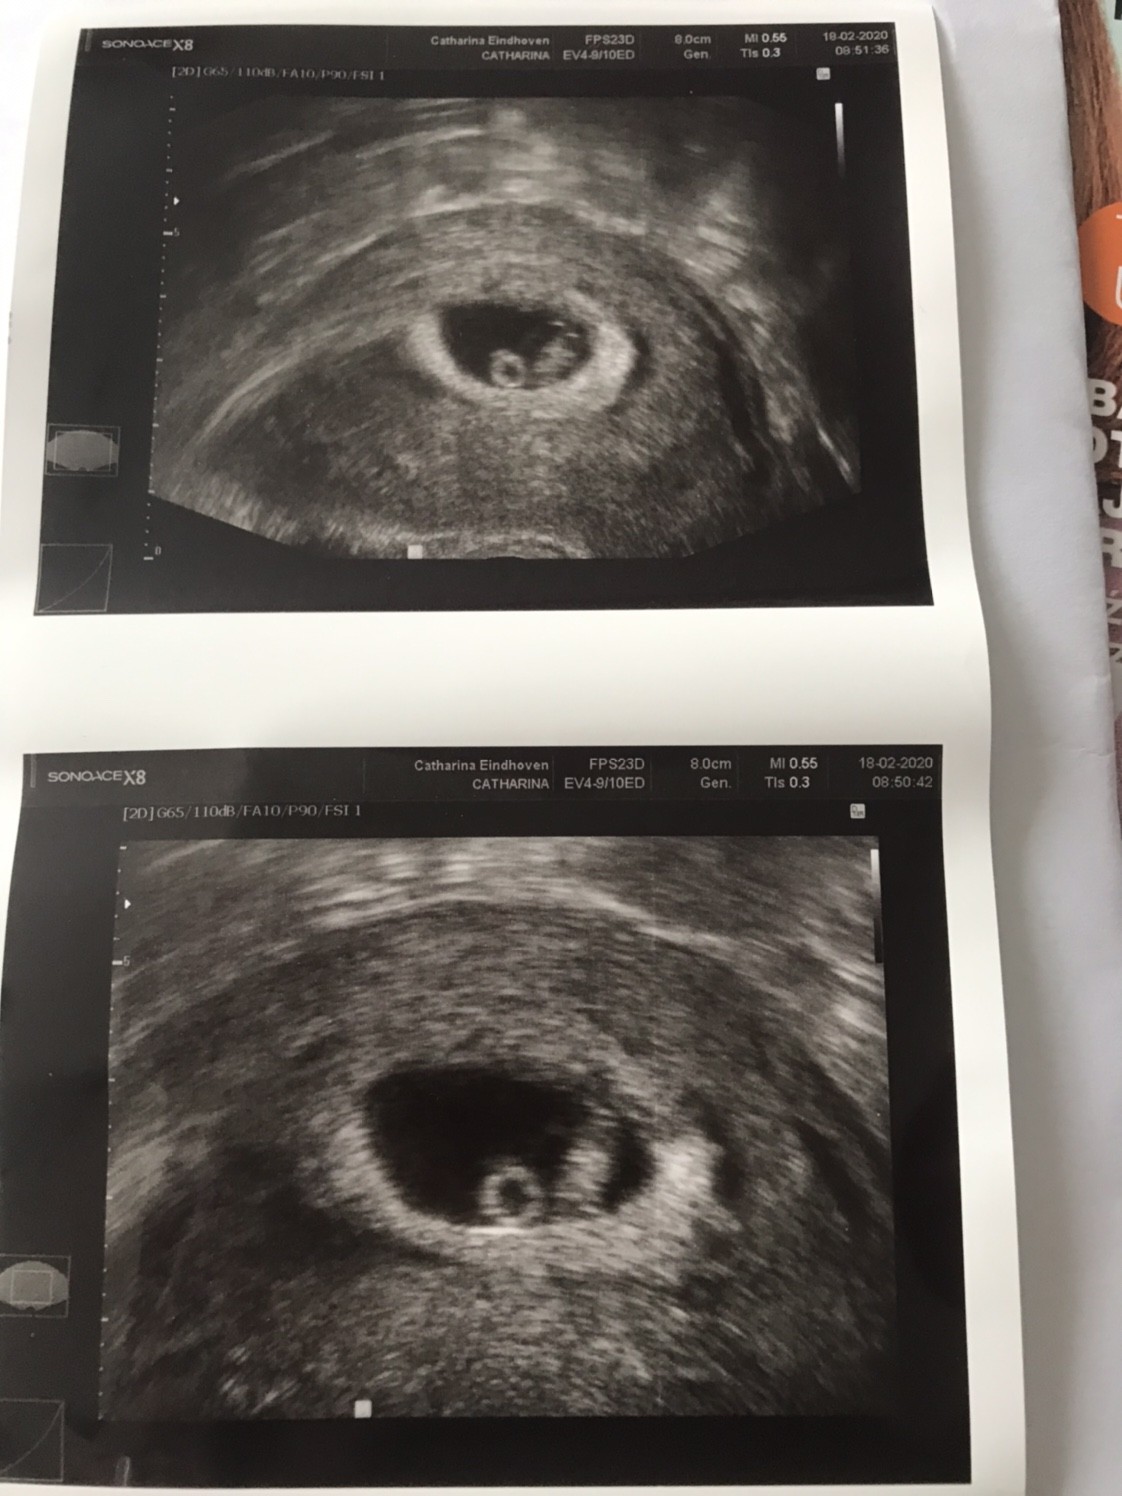

Dziewczyny - takie emocje!!!!! [emoji173]️[emoji173]️[emoji173]️[emoji173]️

Mamy serduszko - pięknie łomotało w tym małym ciałku. Jak tylko je zobaczyłam to zaczęłam płakać 🥰🥰🥰[emoji7][emoji7]

Maluszek ma 1,12cm co odpowiada 7tygodniowi i 1 dzień.

Następna wizyta 5.03 wtedy już z lekarzem prowadzącym [emoji5]

A to moje maleństwo